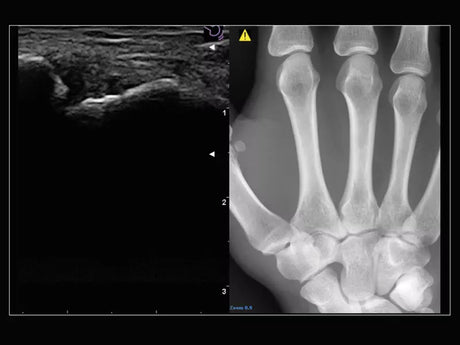

La qualité d’image est au cœur de la philosophie Esaote. Grâce à ses sondes de dernière génération et à son traitement du signal avancé, la marque permet une visualisation fine des structures anatomiques, même les plus profondes. Leurs échographes intègrent des écrans tactiles haute résolution, une interface claire et une connectivité complète, favorisant un flux de travail rapide et efficace.

Les échographes Esaote offrent une restitution d’image d’une grande précision, permettant un diagnostic fiable dans toutes les spécialités. Le traitement numérique optimise le contraste et la netteté, réduisant les artefacts et améliorant la détection des tissus pathologiques. Ces performances sont particulièrement appréciées en gynécologie, où la lisibilité des structures pelviennes ou obstétricales est déterminante.